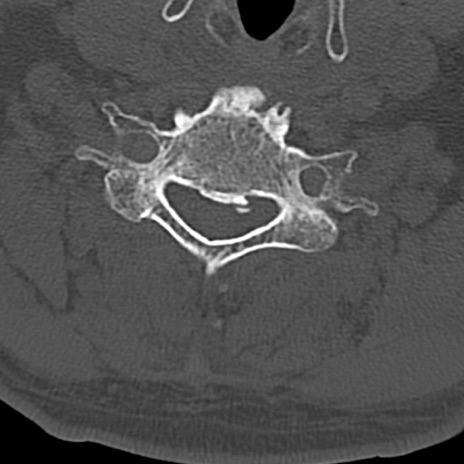

頚椎CT

横断像